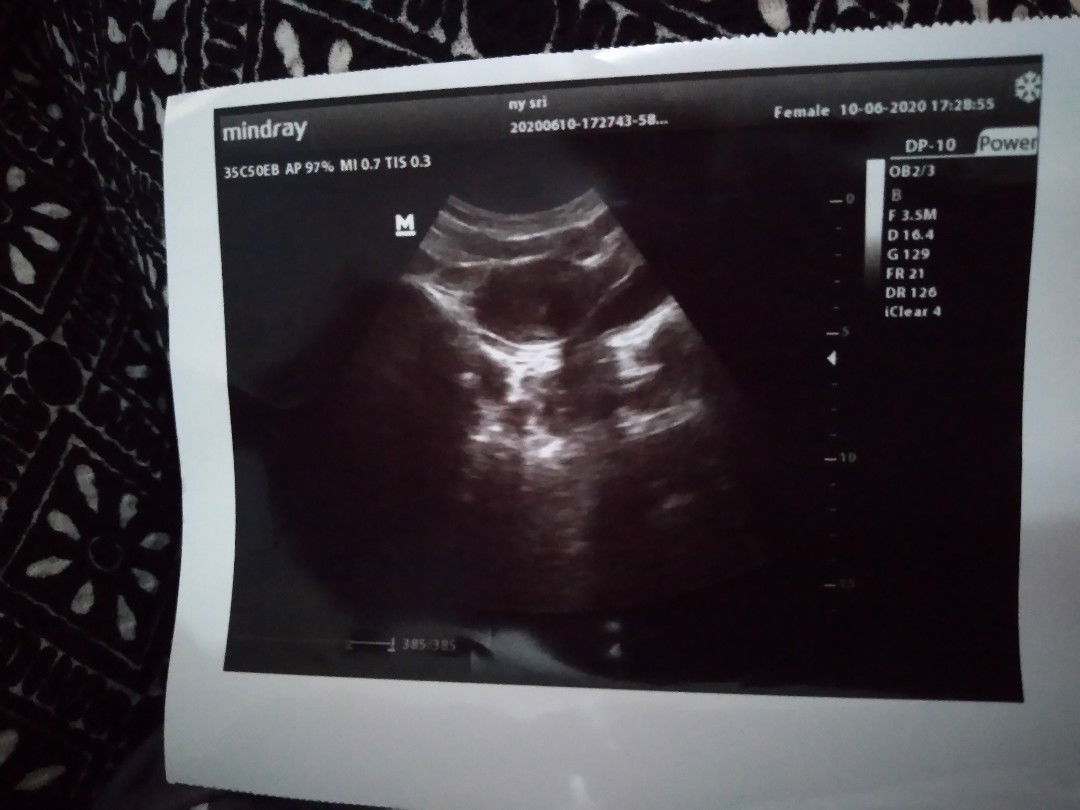

USG kehamilan

Bun mau tanya ada yg paham bisa lihat hasil USG saya yang baru 5 Minggu, Soalnya saya USG di beda tempat katanya gada calon baby nya, Sedangkan saya udah telat 2 Minggu sampe sekarang ini saya belum haid lagi dan Belum pernah KB Bun.. Mohon sarannya Bun soal saya masih awam banget

ditunggu 1 bulan lagi aja bun usg ulang, karna memang usia segitu biasanya baru terlihat kantung kehamilannya saja